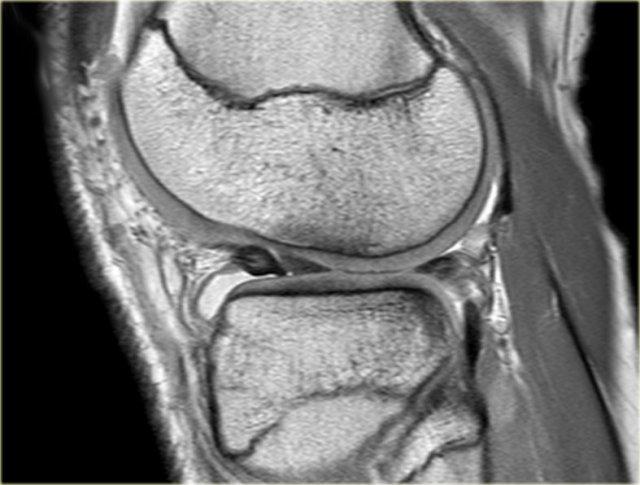

Hình bên trái là một sụn chêm khác với tăng tín hiệu lan tỏa tại thân sụn chêm.

Trên các lát cắt khác (không hiển thị) không có bằng chứng của rách sụn chêm.

Lưu ý tình trạng thoát vị sụn chêm nặng vượt ra ngoài bờ mâm chày.

- Dấu hiệu sụn chêm trong sụn chêm và thoát vị phần giữa sụn chêm (mũi tên đỏ).

- Rách xuyên tâm hoàn toàn tại sừng sau.

Lưu ý thêm hình ảnh hoại tử vô mạch. - Lưu ý thêm hình ảnh hoại tử vô mạch.

- Thoát vị sụn chêm kèm hoại tử vô mạch.